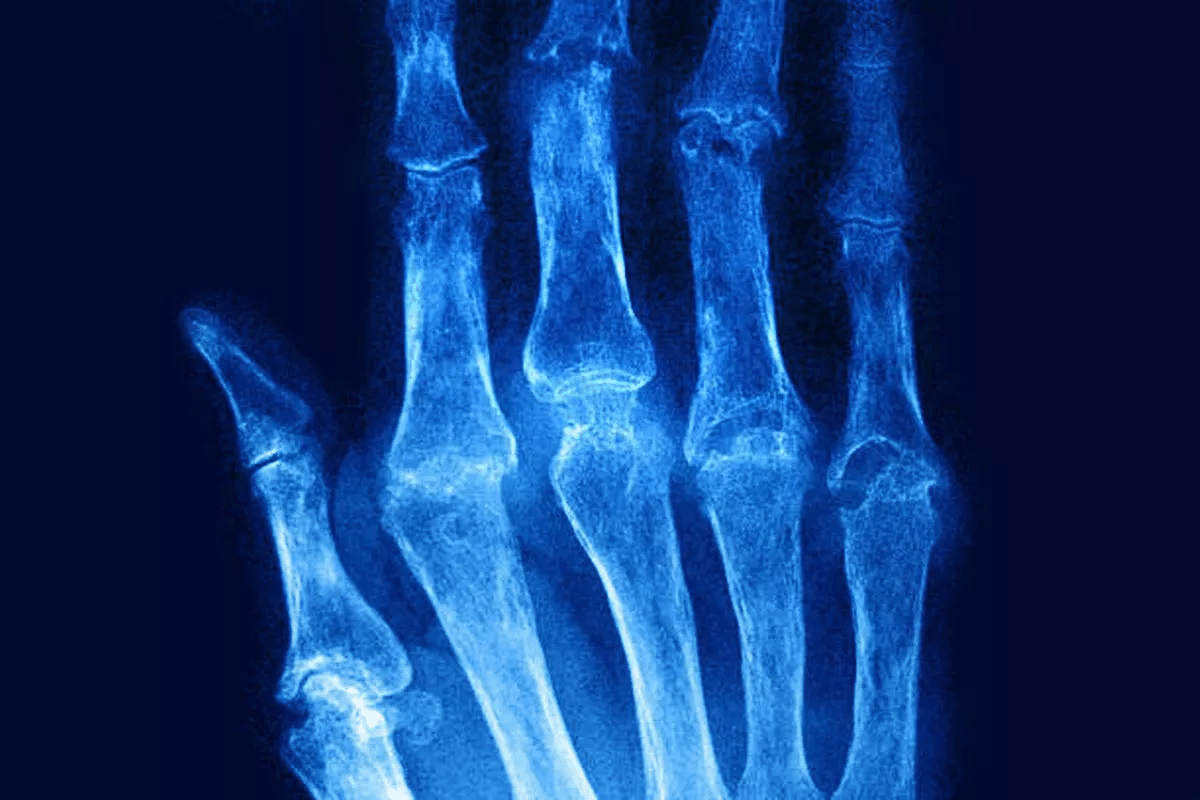

Rheumatoid arthritis (RA) flares are times when the disease gets worse. You might feel more pain, swelling, stiffness, and tiredness. These bad times can happen without warning and really mess up your day-to-day life. At Liv Hospital, we get how tough RA flares can be and how important it is to handle them well.

An RA flare means a spike in disease activity. Symptoms like joint pain and swelling get worse. This makes it hard to move around and feel tired.

During a flare, joints hurt more, and swelling increases. Morning stiffness lasts longer. Feeling tired is common, due to the disease and sleep issues.